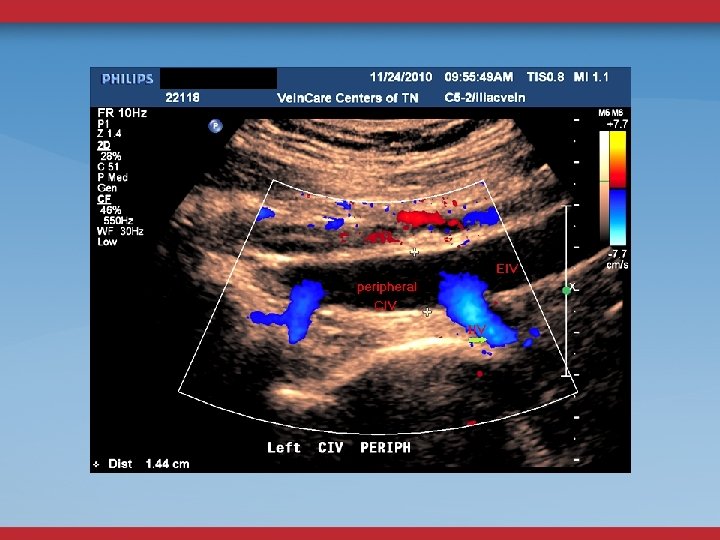

ABDOMINAL/PELVIC DUPLEX FLOW AND ANATOMY STENOSIS MINOR DIAMETER REDUCTION ELEVATED PEAK VENOUS VELOCITY RATIO >2. 5 FLOW REVERSAL GONADAL, ASCENDING LUMBAR, PELVIC VARICOSITIES

80% OF ILIOFEMORAL DVT HAVE AN UNDERLYING EXTRINSIC ILIAC VEIN COMPRESSION Chang, et al. JVIR; 15: 249 -56.

MAY-THURNER IVC FILTER OCCLUSION ANEURYSMS, ARTERIAL GRAFTS TUMORS, CYSTS SURGICAL INJURY RADIATION FIBROSIS HYPOPLASTIC KLIPPEL-TRENAUNAY